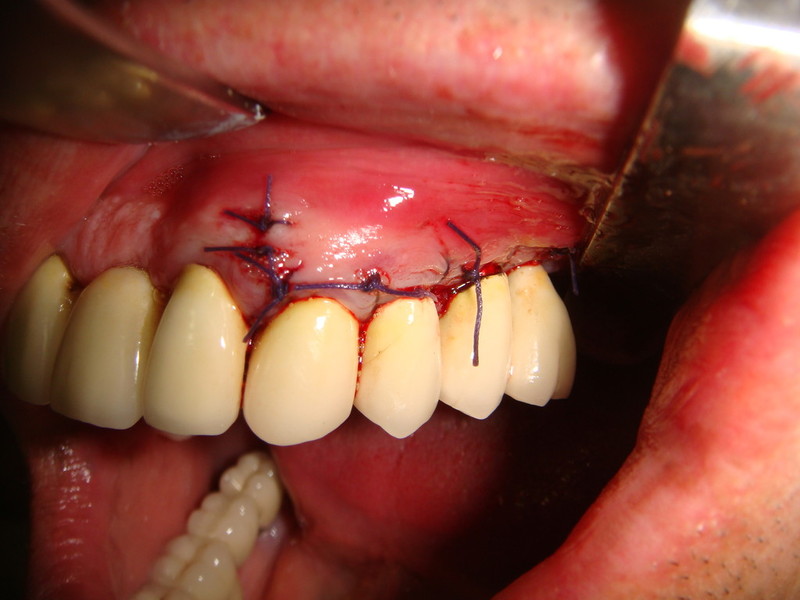

Chirurgia plastica Muco-Gengivale

Impianti Post-estrattivi con innesto di osso e tessuto epitelio-connettivale

Estrazione radice e inmnesto Epitelio-Connettivale